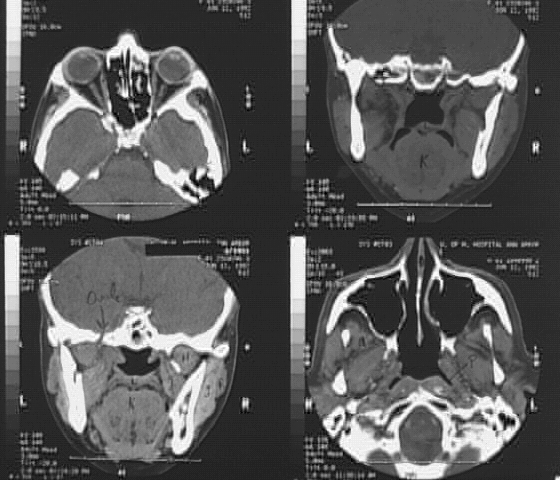

Head & Neck:Head CT Orbits 1: